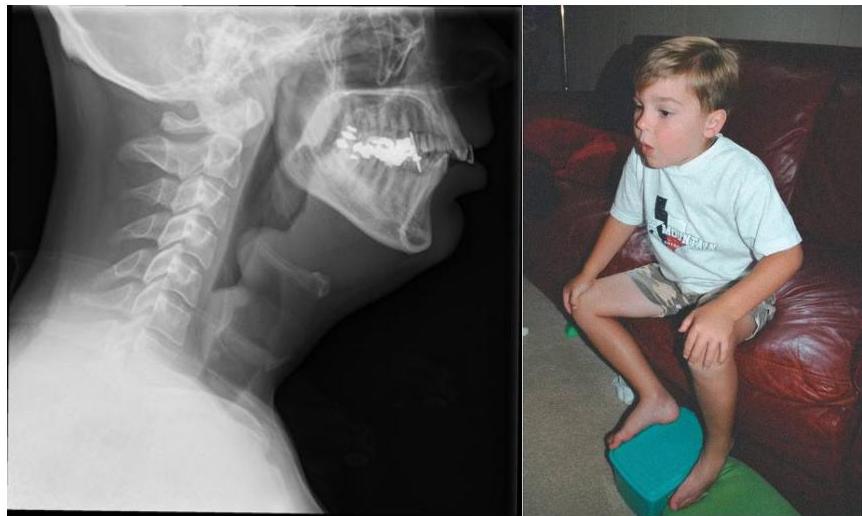

Acute Epiglottitis

Station recall: Video about epiglottitis and how to manage.

Scenario: 3 year old non-vaccinated boy presents with fever, worsening sore throat, and respiratory distress. Exam reveals toxic appearing child, temp 40°C, drooling of saliva, stridor and sitting in tripod position (trunk leaning forward, neck hyperextended, chin thrust forward).

Q1: What is likely diagnosis?

- Acute epiglottitis

- Finding: Thumb sign (on lateral view)

Q2: How do you manage?

- Emergency airway management in the Operating Room (OR) with anesthesia/ENT

- Call the Anesthesia team and prepare for Endotracheal intubation

- First management: intubation and tracheostomy if failed

- All patients should be monitored in ICU

- IV Antibiotics

- Give Rifampin for close contacts

Causes: Staph most common (Streptococcus pneumoniae + Group A strept) if vaccinated, or Haemophilus influenzae type B if not vaccinated

Croup (Laryngotracheobronchitis)

Radiographic Sign: Steeple or pencil sign of the proximal trachea

- Egg on string appearance - EGG ON SIDE, generalized cardiomegaly, Narrow mediastinum Description: Knee chest position (Squating position) to treat the episodes of TOF

Squatting

- Common with unrepaired TOF

- Increases oxygen saturations

- Angulation and kinking of femoral arteries with increased SVR, decreasing the R→L shunt